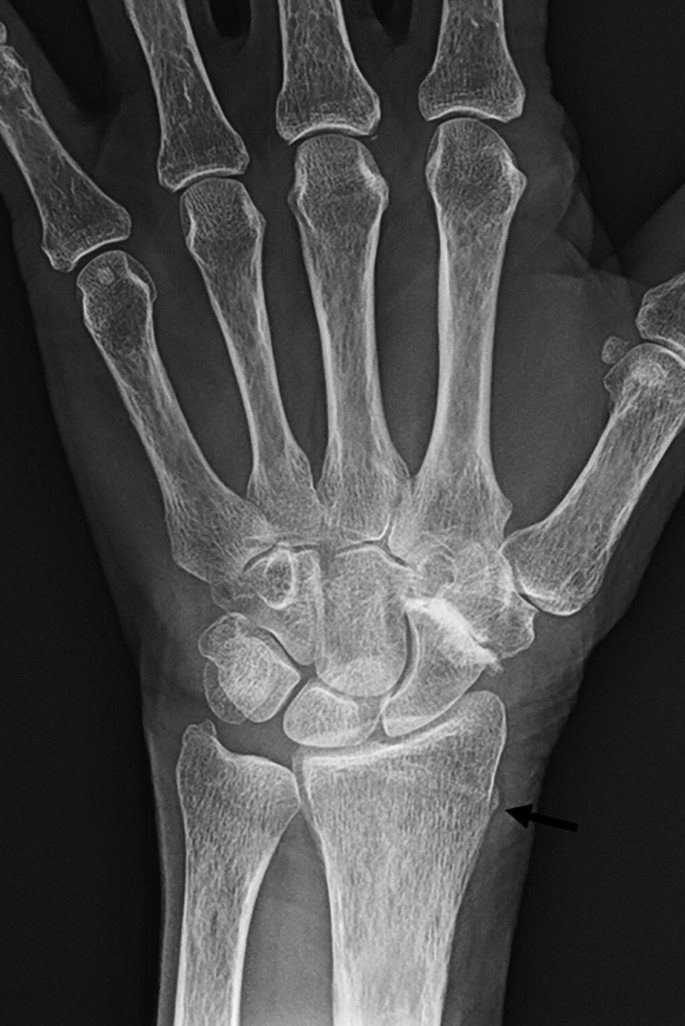

Diagnosis of Hand & Wrist